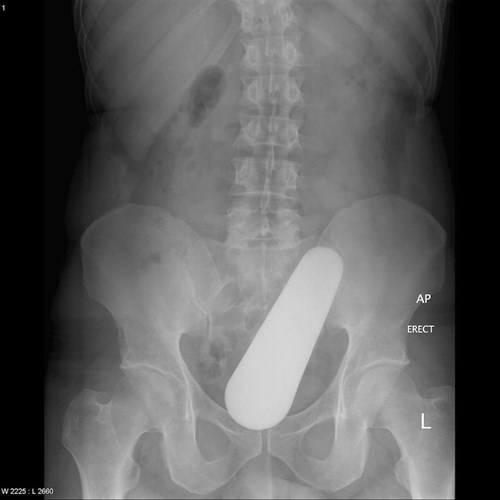

| Phim chụp của người đàn ông ở Malaysia bị mắc kẹt một chiếc chày khi anh ta đang nấu ăn. |